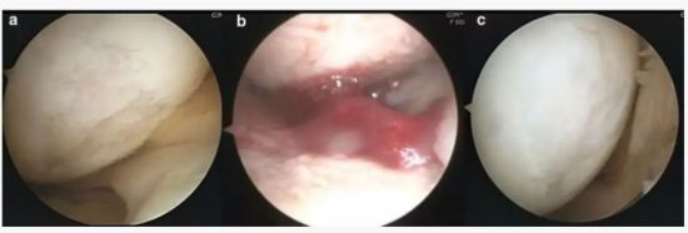

下图a为治疗前关节镜检查结果,,,可以看出软骨存在缺损。。图b为脂肪间充质干细胞联合PRP治疗,,,,图c为治疗后结果,,,通过间充质干细胞治疗,,,软骨得到了修复。。。

image.png